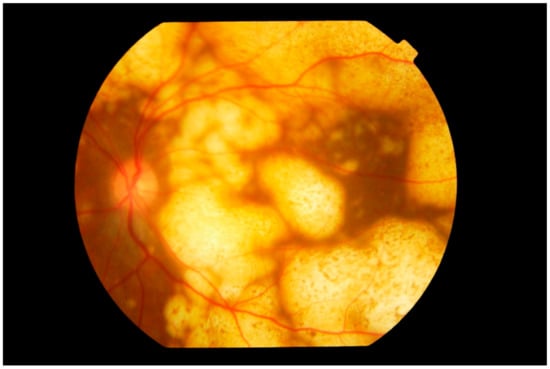

4.1. Imaging

4.1.1. Fundus Autofluorescence

4.1.2. Spectral Domain Optical Coherence Tomography

4.1.3. Fluorescein Angiography

4.1.4. Indocyanine Green Angiography